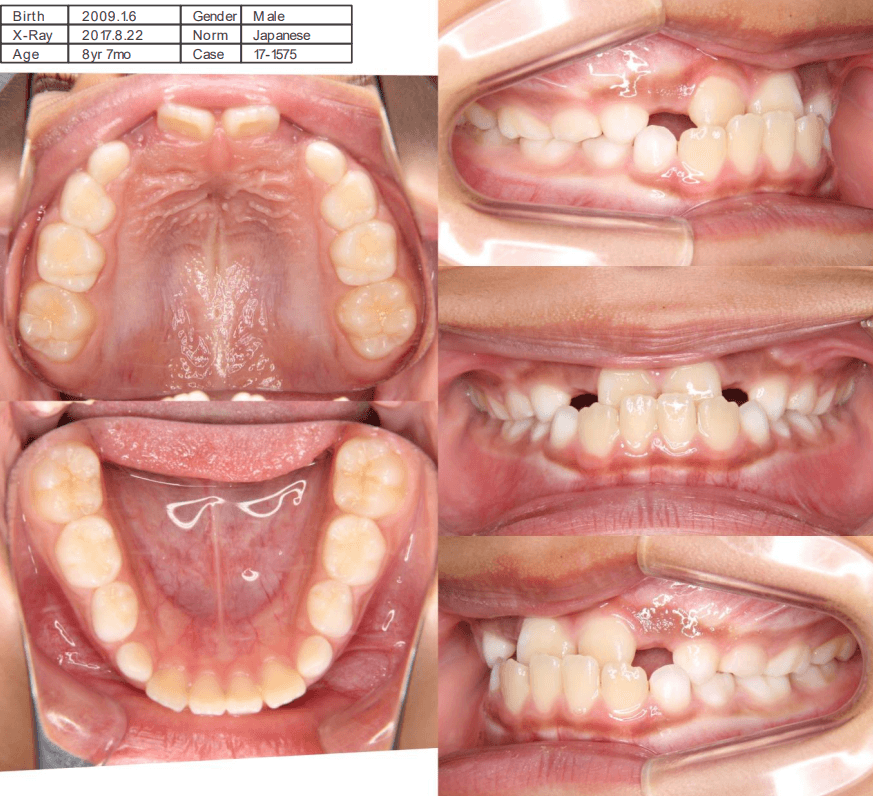

早期矯正治療 反対咬合症例①

主訴 | 前歯がうまく噛み合わず、食事時に違和感があるとのことで来院されました。保護者様からは、将来的な歯並びの不安についてもご相談がありました。 |

---|---|

診断結果 | 8歳7か月の男児 前歯の反対咬合(下顎前突)診断 |

治療内容 |

|

治療後の経過 | 動的治療は1年3か月で完了。反対咬合は改善されました。現在は3〜4か月ごとの定期検診で経過観察中で、今後本格的な矯正治療へ移行予定です。 |

治療期間 | 動的治療期間:1年3か月 治療回数:11回 |

治療費用 | 400,000円(税別) |